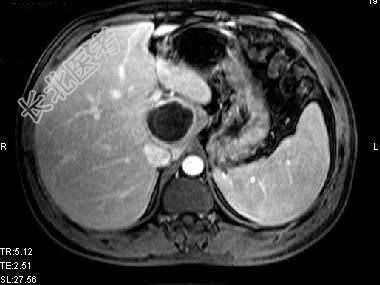

单项选择题根据所提供的图像,最可能的诊断是 ( )

A、肝囊肿

B、胆管细胞癌

C、先天性胆管扩张

D、肝脓肿

E、以上都不是